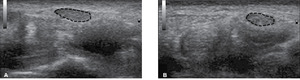

Przyczyną tej najczęstszej mononeuropatii jest ucisk nerwu pośrodkowego w kanale nadgarstka, spowodowany stanem zapalnym nerwu, zmianami zwyrodnieniowymi lub rzadziej pourazowymi (np. po złamaniu stawu promieniowo-nadgarstkowego). Główne objawy to uczucie mrowienia i drętwienia w obrębie nadgarstka, palca wskazującego i środkowego, dodatnie objawy Tinela i Phalena, zanik mięśni kłębu kciuka, osłabienie siły i precyzji ruchów dłoni. Z ultrasonograficznego punktu widzenia istotnym elementem patofizjologii jest wtórny do niedokrwienia związanego z uciskiem, obrzęk nerwu pośrodkowego, zaznaczony najbardziej w odcinku tuż przed wejściem do kanału nadgarstka. Dlatego najważniejszym punktem ultrasonograficznej diagnostyki zespołu cieśni nadgarstka jest ocena pola powierzchni przekroju poprzecznego nerwu (cross-section area, CSA) (ryc. 2). W klasycznej publikacji Buchbergera i wsp. z 1991 roku4 do pozostałych ultrasonograficznych objawów zespołu cieśni nadgarstka, poza powiększeniem pola powierzchni przekroju poprzecznego nerwu, zaliczono łukowate wygięcie troczka zginaczy i spłaszczenie nerwu w obrębie kanału.

Celem licznych badań, których wyniki opublikowano w ostatnich latach,5-8 było określenie najwłaściwszego miejsca oceny oraz norm dla pola powierzchni przekroju nerwu. W doniesieniach opartych na największym materiale i o prawidłowej metodologii (rozpoznanie zespołu cieśni nadgarstka zweryfikowane badaniem neurofizjologicznym), kwalifikowanych jako badania klasy 1 i 2 wg AAN (American Academy of Neurology),9 za najlepszą uznano ocenę pola powierzchni przekroju poprzecznego nerwu pośrodkowego tuż przed wejściem do kanału nadgarstka sondą liniową umieszczoną prostopadle do nerwu. Graniczna wartość pola powierzchni przekroju poprzecznego, powyżej której można postawić rozpoznanie zespołu cieśni nadgarstka, była różna i wahała się od 8,5 do 12 mm2. Czułość metody oceniano w zakresie 65-97%, a swoistość od 50 do 98%. Według wspomnianych we wstępie wytycznych AANEM9 dane te sugerują uznanie badania ultrasonograficznego za rekomendowane w rutynowej diagnostyce zespołu cieśni nadgarstka (poziom dowodów A).